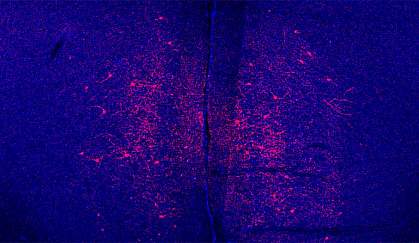

A team of researchers led by Dr. Nathaniel Heintz at Rockefeller University previously discovered a group of oxytocin-responsive brain cells—called oxytocin receptor interneurons—that regulate a social behavior in female mice. To investigate possible sex-related differences of these neurons, the researchers genetically inserted a light-activated sensor into the brain cells of both male and female mice. This allowed the scientists to control the activity of the brain cells with light and observe the animals’ behavior at the same time. The research was funded in part by NIH’s National Institute on Drug Abuse (NIDA). Results were published in Cell on September 22, 2016.

The scientists activated oxytocin receptor interneurons and then compared how anxious or social the mice were during different tasks. The team measured the animals’ behaviors while they explored an open field or an elevated maze or while in a chamber with an unfamiliar mouse of the opposite sex. After the brain cells were activated, male mice became less anxious but the females did not. The female animals did, however, become more social.

The light-activated brain cells project into 2 areas of the medial prefrontal cortex―a brain region responsible for complex behaviors. In male mice, cells in one of the areas responded more robustly to the light activation. Cells in this region were also more sensitive in male animals to a stress hormone called CRH. The researchers determined that oxytocin receptor interneurons released a molecule called CRHBP that blocked the activity of CRH. CRHBP thus reduced the stress hormone’s effect on cells in the male brain. The team found that female mice had higher levels of CRH in their brains. This likely accounts for their lack of sensitivity to CRHBP’s stress-reducing effects.